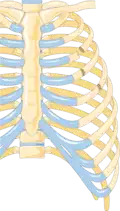

-

Illustration showing rib fracture at 3rd, 4th and 5th rib -